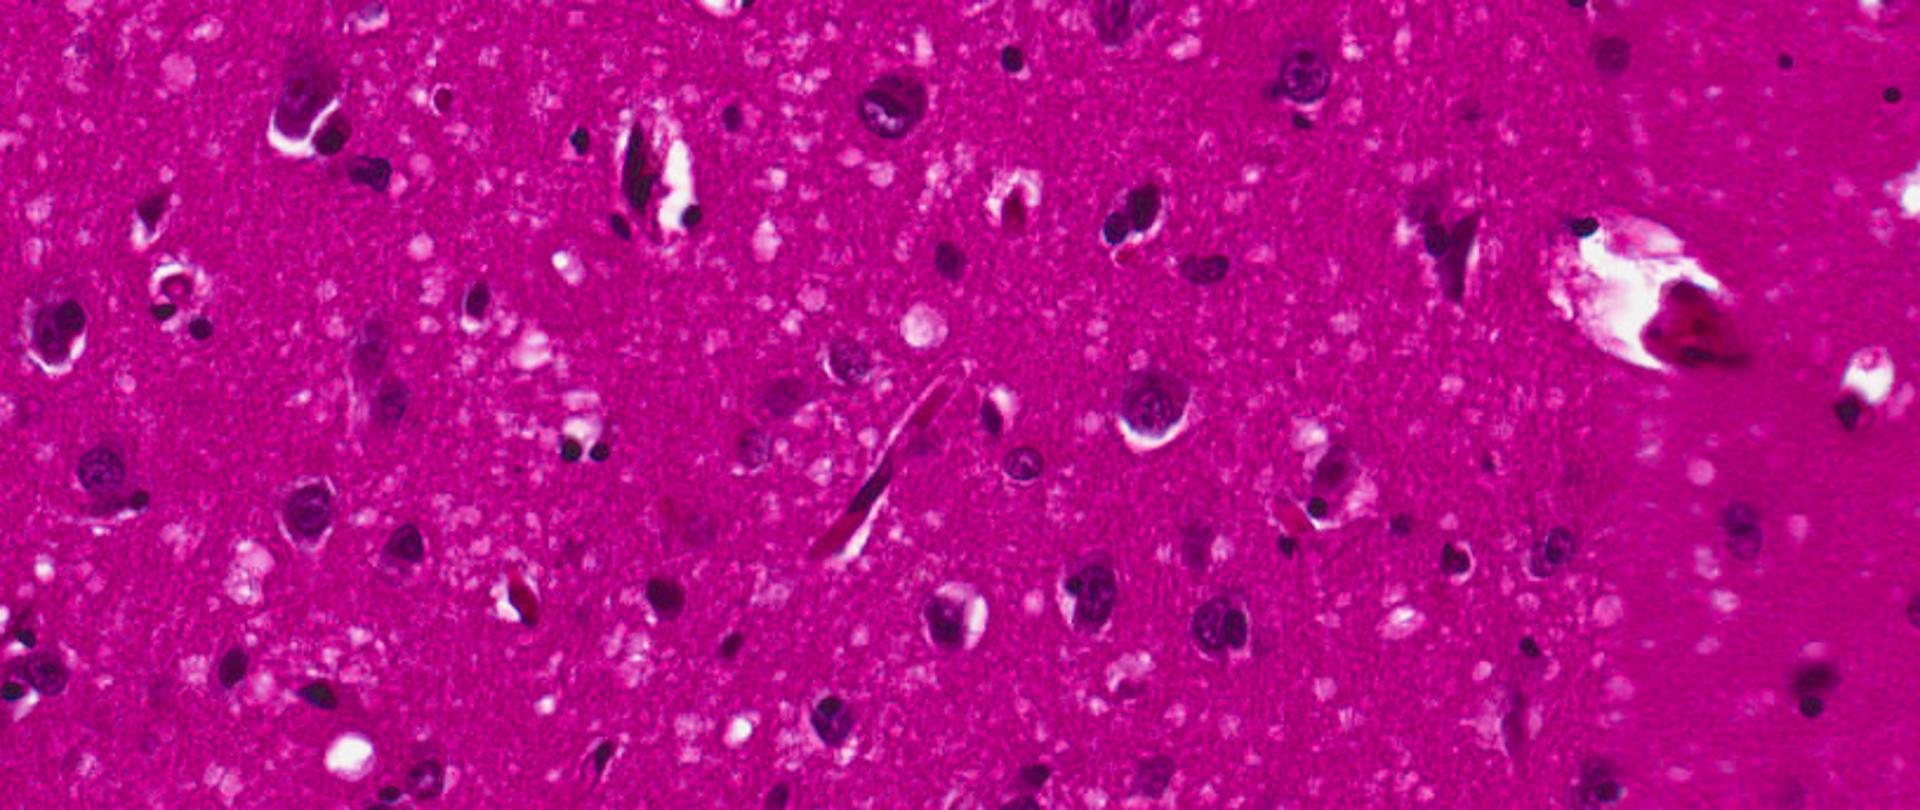

Choroba Creutzfeldta-Jacoba (CJD) jest rzadko występującą, śmiertelną chorobą ośrodkowego układu nerwowego. Zaliczana jest do tzw. pasażowalnych (zakaźnych) encefalopatii gąbczastych. Choroba ta występuje najczęściej pomiędzy 50, a 70 rokiem życia.

Choroba Creutzfeldta-Jakoba zaliczana jest do schorzeń bardzo rzadkich, co zobowiązuje diagnostów w pierwszej kolejności do wykluczenia częściej występujących przypadłości. Jest przypadłością, która atakuje ośrodkowy układ nerwowy, przyczyniając się do zwyrodnienia mózgu. Może mieć ona podłoże genetyczne, a także pojawiać się w skutek zakażenia, po kontakcie z brudnymi narzędziami chirurgicznymi lub w skutek spożywania zakażonego mięsa. Choroba ta jest niestety nieuleczalna, istnieją jednak środki stosowane objawowo, które mają na celu zwiększyć komfort życia.